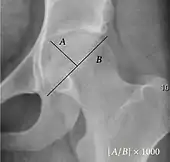

Reimer's migration index.

• Reimer's migration index (MI), also called the femoral extrusion index,[3] is calculated if hip dysplasia is detected. It can be used to indicate hip dislocation. It is the horizontal distance (parallel to the Hilgenreiner Line) between the Perkin line and the lateral border of the ossification center of the femoral head, divided by the horizontal width of the ossification center. The migration index is normally less than 33% by most sources,[9] but 25% and 30% has also been suggested.[10]